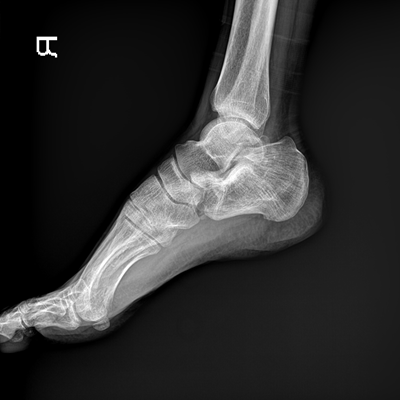

高品質(zhì)影像鏈 讓您看的更清晰 PLX8500C/D

●大尺寸非晶硅平板探測器。

●非晶硅平板探測器,采用先進的制造工藝、性能更穩(wěn)定。

●探測器可以大范圍轉(zhuǎn)動,大尺寸有效探測面積,可滿足人體多部位攝影需求。